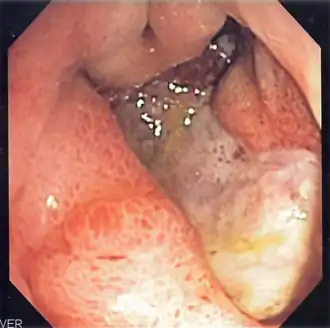

La fibroscopie œsogastroduodénale est l’examen de référence. Elle visualise l’ulcère, en détermine la localisation, s’il est isolé ou multiple. Des biopsies sont nécessaires en cas d’ulcère gastrique, pour vérifier l’absence de cancérisation. Les ulcères les plus fréquents sont situés sur la petite courbure de l’estomac et sur le bulbe du duodénum (partie postérieure). On recherchera également une colonisation par l’Helicobacter pylori, très souvent associé à l’ulcère gastroduodénal, et dont l’éradication permettra d’éviter des récidives.

La fibroscopie peut voir un saignement en cours, ou seulement la présence d'un caillot. Elle peut ne visualiser qu'un ulcère apparemment non compliqué.

- hémorragie : une fibroscopie, réalisée en urgence[19], permet de confirmer la cause gastrique du saignement et de mettre en route un traitement endoscopique adapté. En cas de visualisation d'un caillot adhérent, celui-ci doit être retiré afin de visualiser la lésion saignante et la traiter[20]. Plusieurs types de traitement peuvent être pratiqués : l'injection siloée d'adrénaline n'est plus conseillée[21]. l'injection de liquides dans la muqueuse proche de l'artère responsable permet de comprimer cette dernière et complète ainsi l'adrénaline. La pose d'un clip sur l'artère est une autre solution, équivalente à la thermocoagulation[22]. Ce traitement endoscopique permet de réduire le risque de récidive, le recours à la chirurgie et la mortalité[23]. L'intérêt d'un contrôle endoscopique quelques jours après la guérison d'un saignement est discutable[7]. Une perfusion d’inhibiteurs de la pompe à protons à forte dose est réalisée dans le même temps[24]. La dose nécessaire reste discutée, les fortes doses ne montrant pas de supériorité par rapport à des doses inférieures[25]. Si la visualisation de l’ulcère est impossible du fait des caillots, s’il y a récidive du saignement, ou si celui-ci est trop important, une intervention chirurgicale en urgence permet de contrôler l’hémorragie. Une embolisation de l'artère responsable peut être une solution alternative[26]. Le traitement par inhibiteurs de la pompe à protons sera continué après cette intervention, un contrôle de la bonne cicatrisation de l’ulcère sera nécessaire à six semaines en cas de localisation gastrique (avec biopsies pour éliminer une cancérisation).

Un contrôle endoscopique de la guérison de l’ulcère gastrique sera effectué pour confirmer l’éradication d’Helicobacter pylori, l’absence de gastrite atrophiante, de lésion cancéreuse et la disparition de l’ulcère.